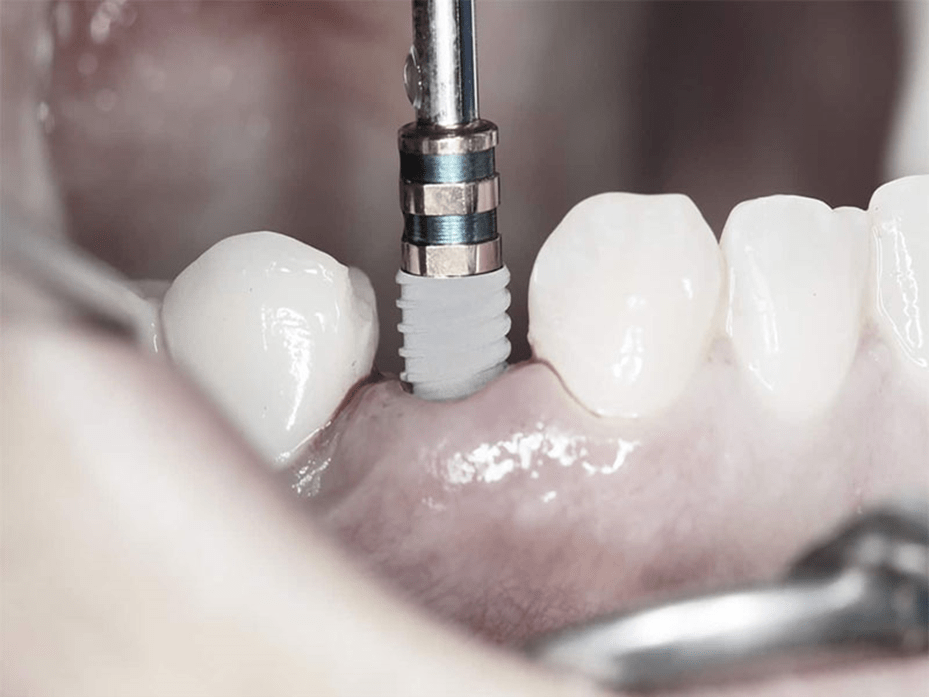

مراحل انجام ایمپلنت به روش پانچ

اگر برای انجام ایمپلنت به روش پانچ به کلینیک دندانپزشکی زیبایی مراجعه کنید، در ابتدا دندانپزشک با استفاده از تصاویر سه بعدی رادیوگرافی ساختار استخوان، لثه و دندانهای شما را به طور دقیق و کامل مورد بررسی قرار میدهد تا در صورت اطمینان از وجود استخوان فک به میزان کافی، نرمی لثه و عدم عفونت و پلاک، اقدام به انجام ایمپلنت بدون درد و جراحی نماید.

در صورت وجود شرایط ذکر شده، دندانپزشک به کمک بیحسی موضعی دهان و لثه بیمار را بیحس کرده و با دستگاههای مخصوص پانچ که سرهایی با اندازههای متفاوت دارند، سوراخهایی را با عمق لازم برای کاشت دندان ایجاد مینماید تا پایههای ایمپلنت دندان از جنس تیتانیوم را درون لثه قرار دهد. در انتها نیز توسط دستگاههای خاص سوراخهایی که برای نصب ایمپلنت به روش پانچ ایجاد شده بود، ترمیم میشوند. همین امر موجب میگردد تا به دلیل عدم جراحی و باز شدن لثه، زمان جوش خوردن استخوان فک به پایه ایمپلنت کوتاهتر شده و روند بهبودی سریعتر طی شود.